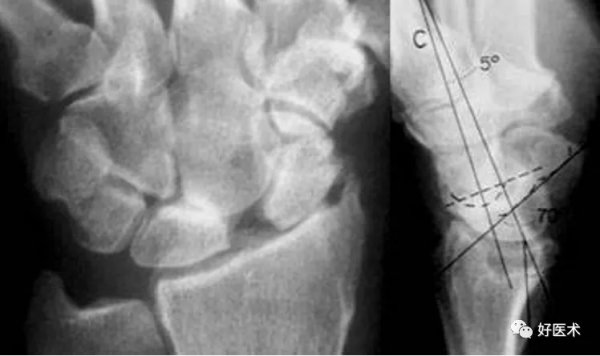

a.橈骨縱軸線b.橈骨縱軸線垂線 c.橈骨遠端關節面切線 d.舟骨軸線 e.月骨軸線 f.頭狀骨軸線

A橈骨前傾角

A.正常為0~20˚。若此角度改變,提示橈骨遠端骨折。

①橈月角(-15° ~ 15°);

②橈舟角(30°~60°);

③舟月角(30°~60°);

④頭月角(-15°~15°)。

在腕骨脫位、半脫位及腕關節失穩時,腕角表現異常。